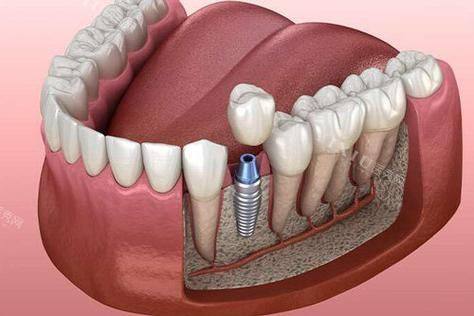

3. 种植牙技术:陈俊龙医生在种植牙方面有着独特的技术优势。他发明的陈氏五合一植牙法结合了多项植牙专项,为患者提供了更效率高、更安心的种植牙解决方案。这种植牙法能够缩短种植时间,提高种植成功几率,让患者更快地修复牙齿功能。同时,他还发明了HSC陈氏水压法鼻窦增高术和VTT陈氏牙龈拉皮法,为种植牙手术提供了更好的基础条件。

1. 创新的技术发明:陈俊龙医生发明了HSC陈氏水压法鼻窦增高术、VTT陈氏牙龈拉皮法和陈氏五合一植牙法等多项技术。这些技术的发明为相关疾病的治疗提供了新的思路和方法。例如,陈氏五合一植牙法结合了多项专项技术,能够提高种植牙的成功几率和效率,减少患者的痛苦和治疗时间。

3. 个性化治疗方案:陈俊龙医生会根据患者的具体情况制定个性化的治疗方案。在治疗过程中,他会充分考虑患者的年龄、身体状况、病情重度程度等因素,选择更适合患者的治疗方法。例如,在种植牙手术中,他会根据患者的口腔情况和需求,选择合适的种植体和种植方案,确保手术的成效和安心性。

3. 患者王先生牙齿缺失多年,一直想进行种植牙手术。他了解到陈俊龙医生在种植牙方面有独特的技术,于是找到了陈医生。陈医生根据王先生的口腔情况,采用陈氏五合一植牙法为他进行了种植牙手术。手术非常顺利,术后王先生的牙齿修复了正常的功能。王先生评价说:“陈医生的种植牙技术真的太棒了,手术时间短,成效还好。现在我又可以正常吃东西了,生活质量提高了特别多。陈医生是一位非常值得信赖的医生。”